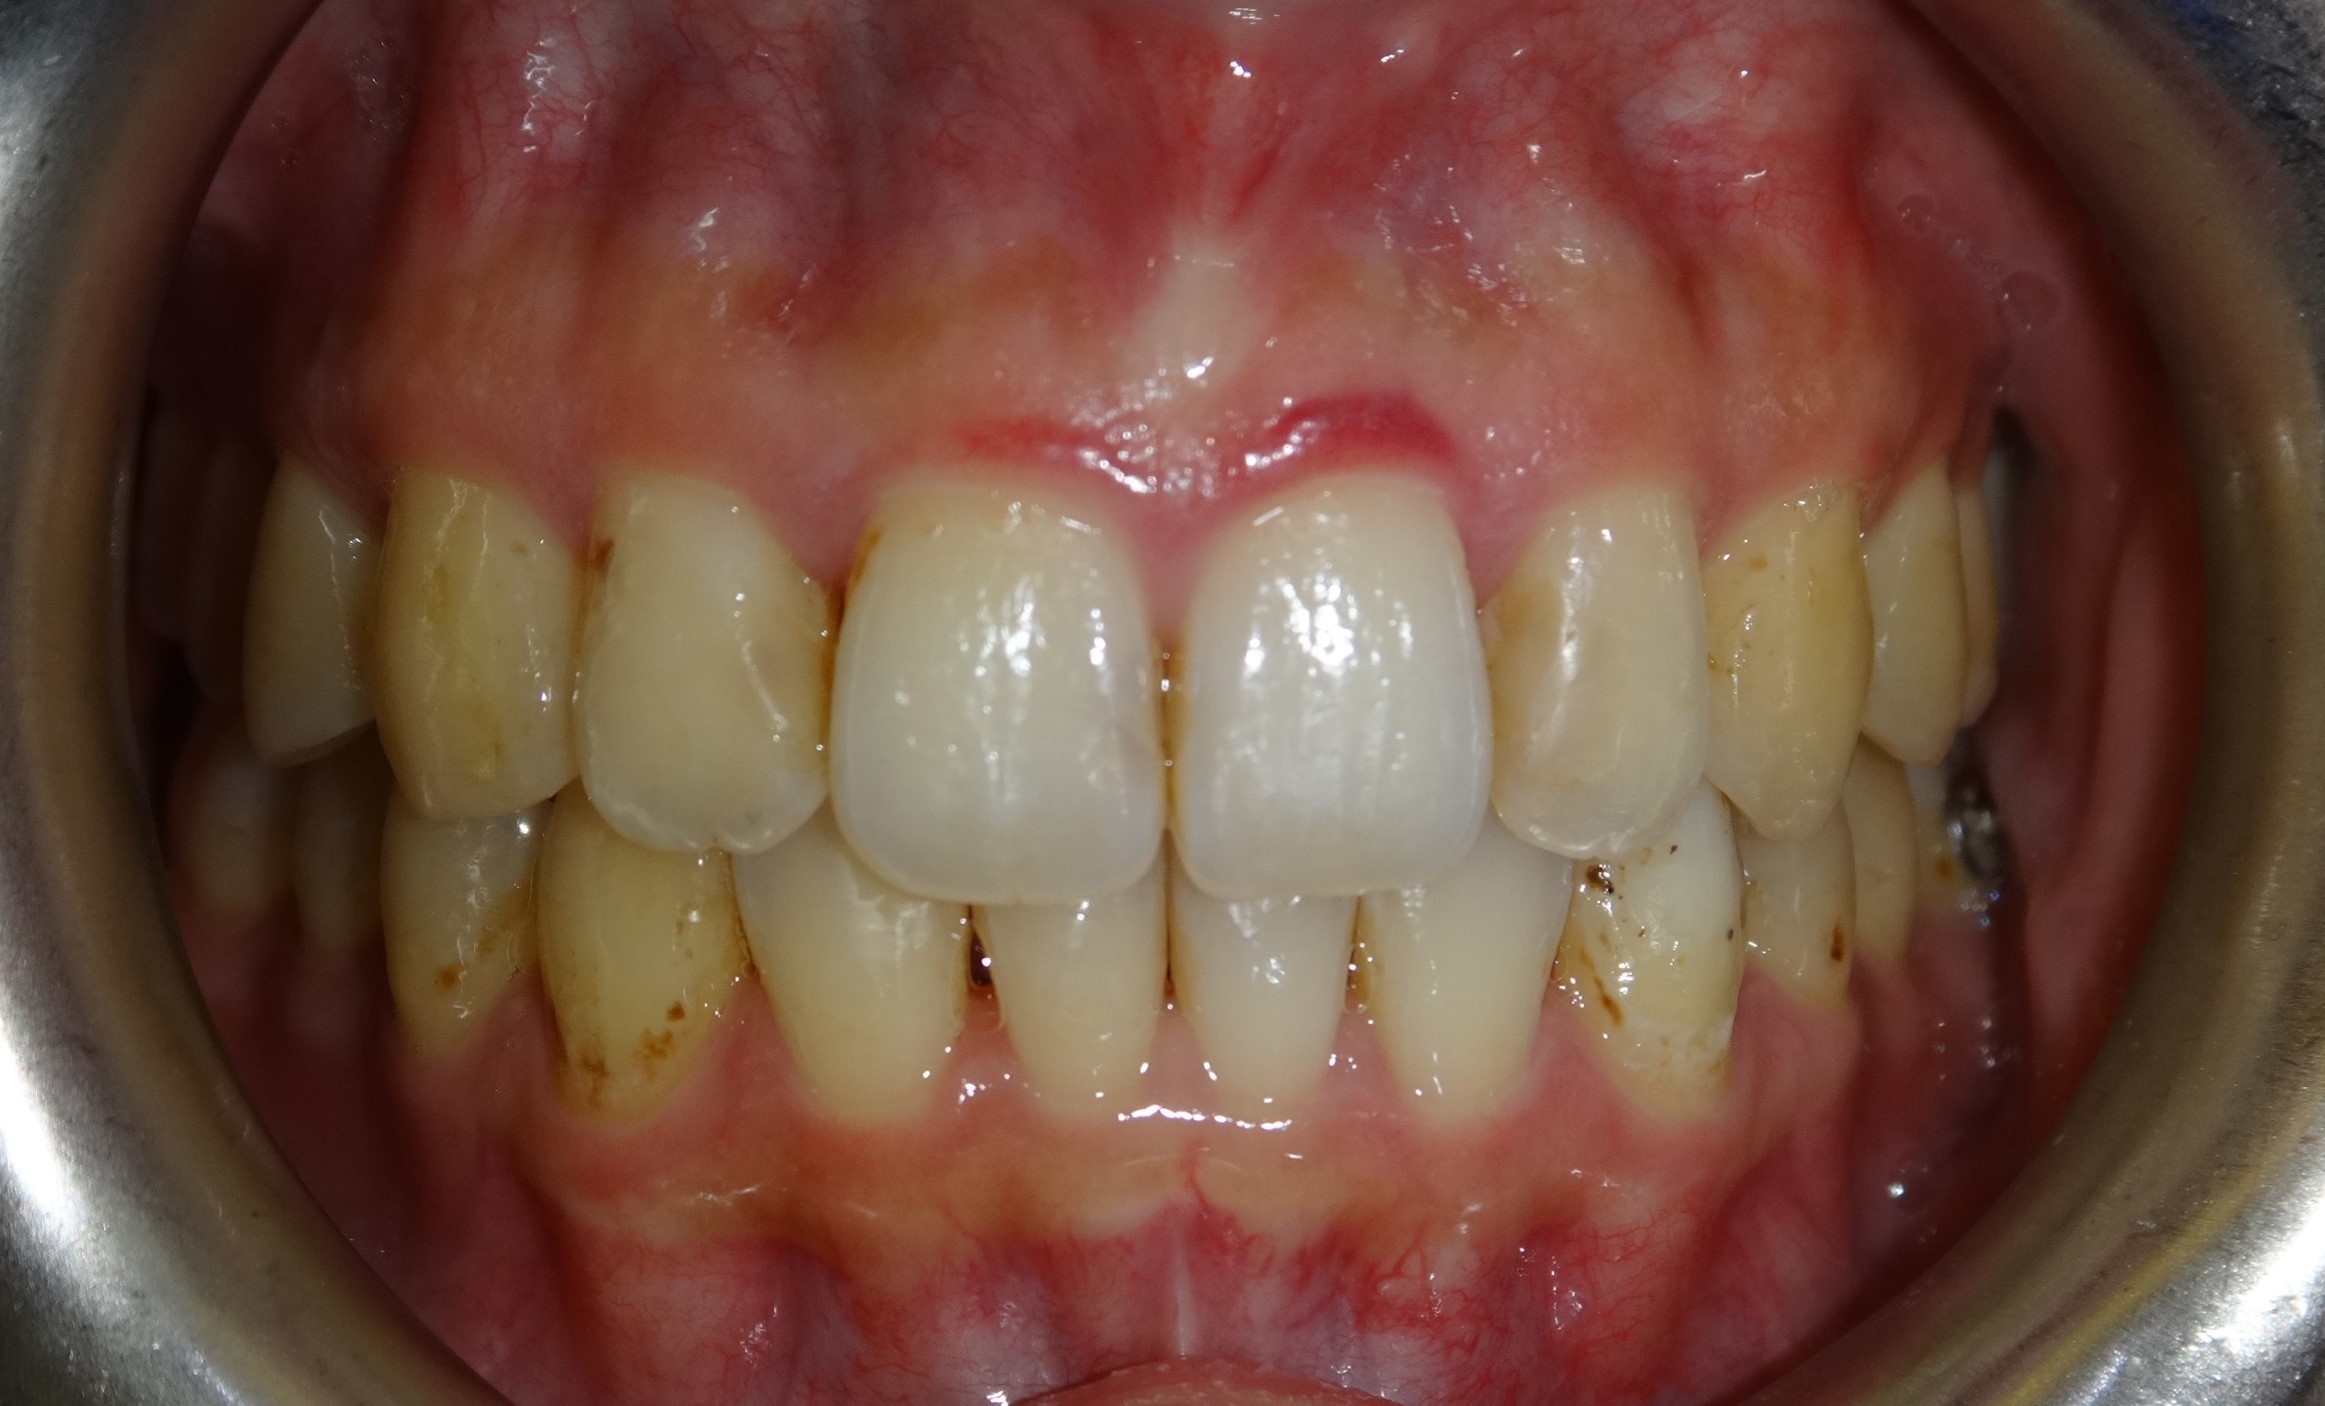

微矯正案例 首頁 案例分享 齒顎矯正 微矯正案例 矯正前 矯正後 - 不拔牙案例 - 年紀:29歲 矯正方式:隱適美隱形矯正 時間:18個月 矯正訴求:門牙外凸、中線不正 聲明:本所療程皆由專業醫生評估後,依照個人口腔狀況進行治療。因每位患者個別狀況不同,術後狀況也不盡相同,需親來本所由醫生評估。